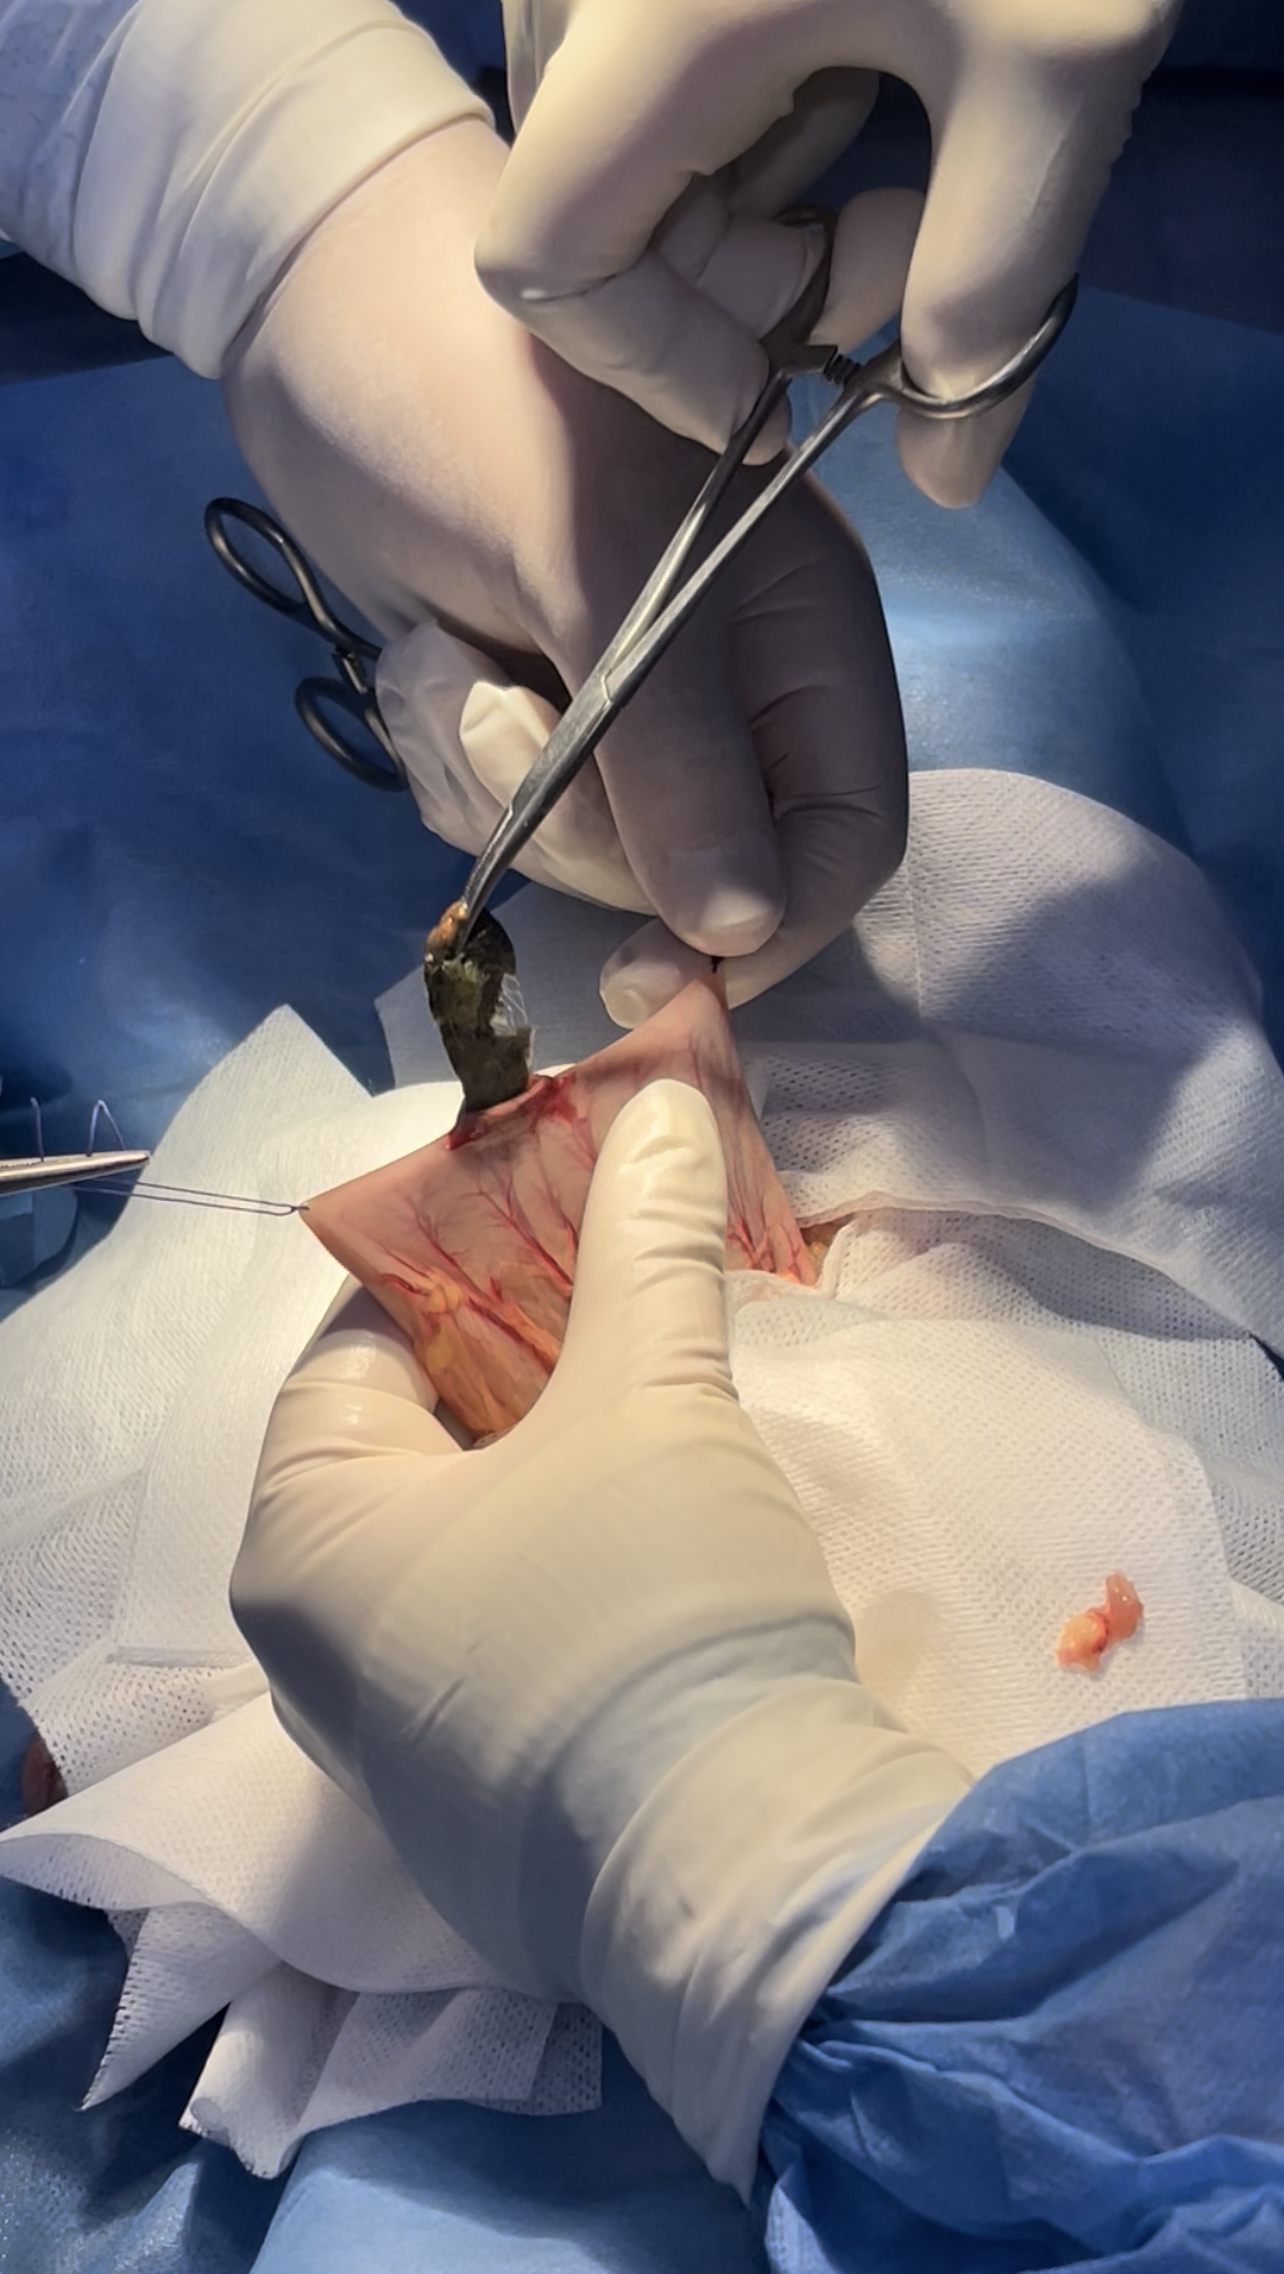

Ventral midline incision extended from the xiphoid to the umbilicus

Fb causing improper emptying of the stomach

Isolation preventing contamination of the field

Stay sutures are helpful in organ manipulation

incision site between the greater & lesser curvature avoiding vasculature

Stapp incision is primary made

further more extension is made as needed

Removal of the clogged hair clumps